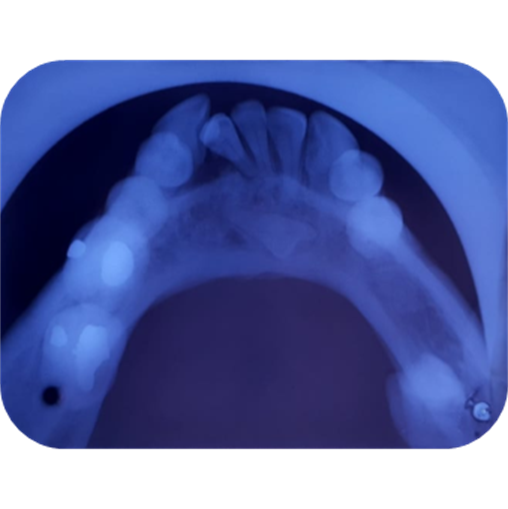

Imagen 1. Fotografías intraorales

El estudio radiográfico puede evidenciar múltiples sombras radiopacas rodeadas de un halo radiolúcido pertenecientes a un tumor odontogénico CIE10: D164 (odontoma compuesto), localizados en a nivel de los órganos dentarios 4.3; 4.1; 3.1; 3.2; 3.3. También se puede constatar la presencia de una sombra radiopaca que concuerdan con el órgano dentario retenido.

Imagen 4. Oclusal Inferior.

El diagnóstico y tratamiento oportuno que se debe tener frente a las neoplasias odontogénicas que son frecuentes en la consulta odontológica, y la mayoría de casos pasa desapercibido nos hacen tomar conciencia de lo importante de tratar , guiar a los pacientes que visitan la unidad de atención odontológica Uniandes a realizarse exámenes complementarios, radiográficos panorámicos, periapicales, oclusales que tienen la posibilidad de demostrar una visión más clara de las estructuras dentarias vecinas, previniendo desarrollos o formaciones de neoplasias ya que, las radiografías las intraorales periapicales, oclusales demuestra mayor fidelidad dimensional en comparación a la panorámica detectando oportunamente patologías que son asintomáticas.

En su gran mayoría en la presentación de este caso clínico se puede observar la presencia de una sombra radiopaca que concuerdan con el órgano dentario retenido 4.2.con una imagen mixta con múltiples radiopacidades muy similares a los órganos dentarios que están rodeados de un halo radiolúcido perimetral que son similares descripciones de investigaciones de otros autores.

Los exámenes radiográficos son de gran valor en el diagnóstico oportuno de neoplasias odontógenas principalmente las de mayor fidelidad como las radiografías periapicales y oclusales.